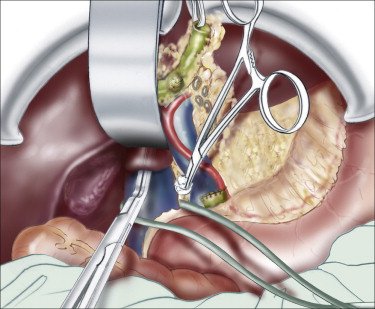

We use advanced imaging and lab tests to ensure safe planning before surgery.

The left lobe is carefully removed using modern surgical tools to minimize blood loss and protect nearby structures.

Only the diseased portion is taken out, keeping as much healthy liver as possible.